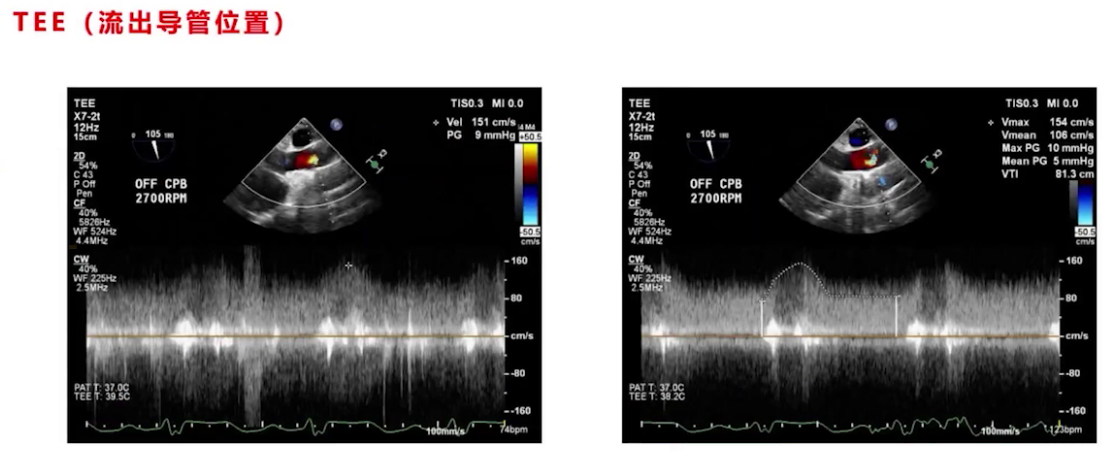

停机前TEE评估无气体,泵头及流出导管位置良好,调节过程中监测心室大小、室间隔形态及心功能,最终转速设为2700转,左室大小从术前71/72降至67左右,右心功能较术前稍有改善。